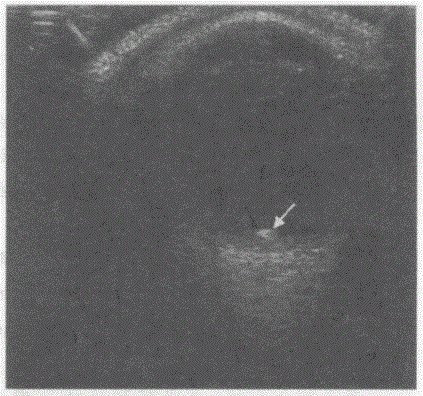

问题 临床资料:男,29岁,采石场工人,施工时异物击中右眼4小时。 超声综合描述:眼球形态、大小正常,晶状体内透声清亮,横切眼球壁6:00玻璃体内见增强回声光点(箭头所指),后方无声影,其旁可见点、小片状低回声,可随眼球运动而移动。 超声提示:

选项 A.眶内异物(金属异物) B.球内金属异物并玻璃体出血、玻璃体混浊 C.眶内异物(碎石屑) D.球内异物(玻璃体内碎石屑)合并玻璃体出血

答案 D